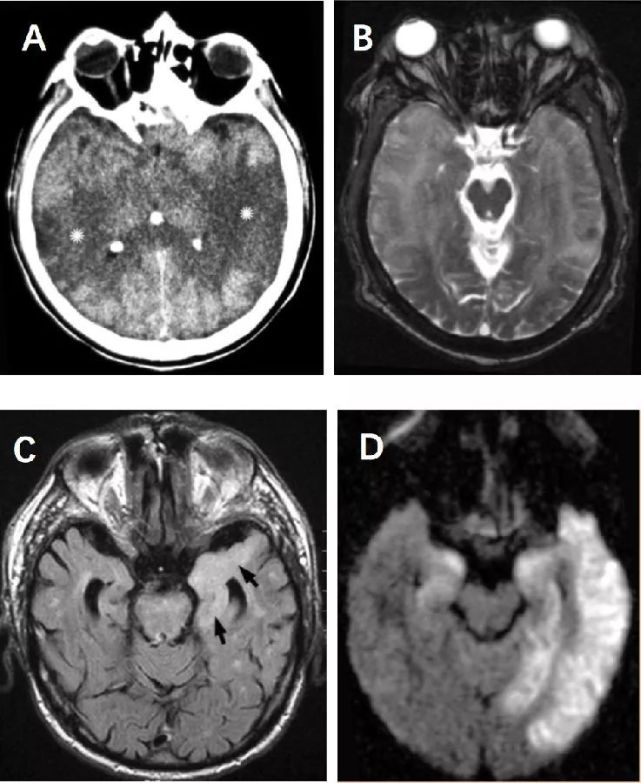

呕吐8天.到目前,我们查到的结果很有趣, [病例帖]

图片尺寸870x712